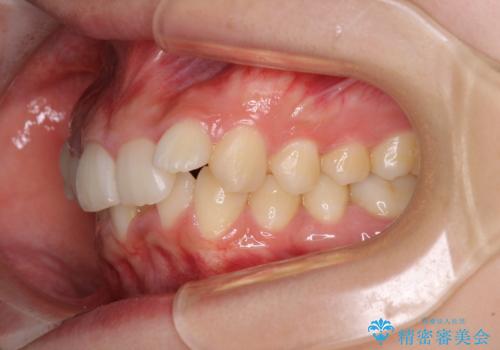

下顎前歯が隠れて突出した口元 ワイヤー装置での抜歯矯正

- 前歯のデコボコと口元の突出感を気にして来院された患者様です。

下顎骨の左右差や、上顎骨の前方位などが認められたため、上下左右の第1小臼歯4本を抜歯し、ワイヤー装置にて矯正治療を行うこととしました。

骨格的な左右差がありましたが、何とか当初予定していた期間で、左右対称の咬み合わせに仕上げることができました。